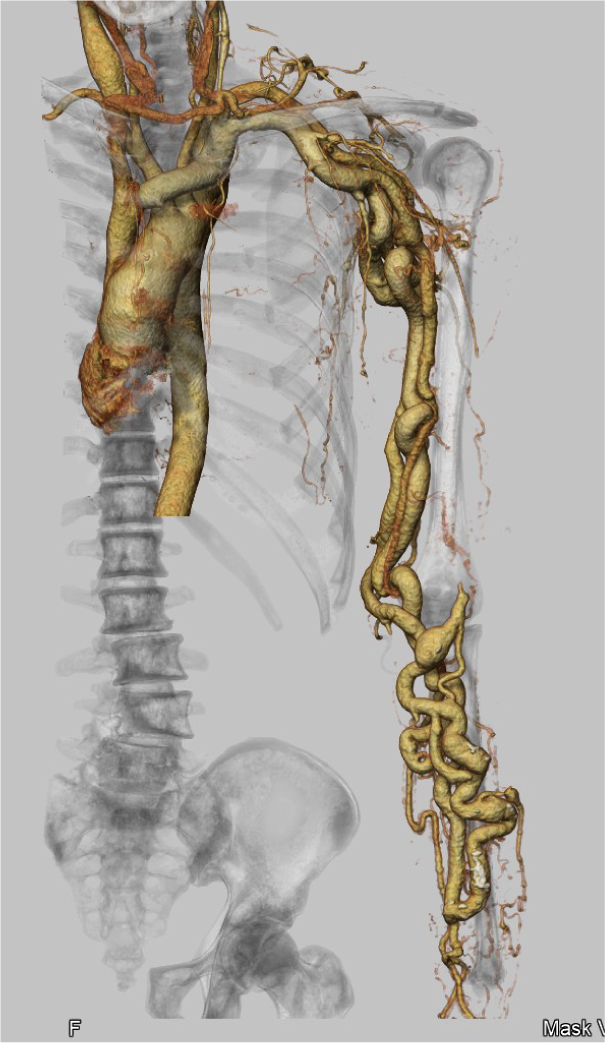

CANON(旧:東芝)社製の80列マルチスライスCTを設置し、胸部・腹部の撮影はもちろん、心臓CTや大腸CT、下肢3DCTといった専門性の高い撮影も行っています。最新のザイオワークステーションを用いて、3D画像作成、心臓解析、大腸の仮想内視鏡検査などを行っています。また、近隣の医療施設からのCT撮影依頼にも対応しており、日々たくさんご利用いただいております。被ばく線量の低減に配慮するとともに、患者さんに合った適切な線量で撮影を行うように心がけています。

前腕CT画像 下肢CT画像